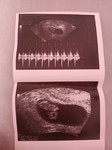

หนูเพิ่งตรวจเจอน้อง 2 ขีดเมื่ออาทิตย์ที่แล้ววันนี่ตอนเย็นหนูเข้าห้องน้ำมันมีก้อนอันนี้ไหลออกมาคืออะไรเหรอค่ะพี่ #ขอคำแนะนำหน่อยค่ะ #ขอบคุณสำหรับคำตอบค่ะ #ขอบคุณล่วงหน้านะคะ #ใครมีประสบการณ์

รีบหาหมอเลยคะเคยเป็นแล้วแต่เลือดไม่เยอะขนาดนี้แค่มีสีน้ำตาลนิดเดียวพอมีก็รีบไปหาหมอพอไปซาวไม่มีเด็กไม่หัวใจไม่มีอะไรนอกจากถุงครรภ์ พอหมอให้กลับมาสังเกตอาการยังไม่ถึงวันที่หมอนัดก็หลุดออกมาเป็นถุงปลาเลยเลือดนิเยอะเลยสุดท้ายได้ขูดมดลูกค่ะท้องลมเสียใจมาก

บอกหมอว่ามีลิ่มเลือดออกมาค่ะ (เอารูปให้คุณหมอดูก็ได้ค่ะ) ตอนนี้เป็นกังวลว่าลูกจะเป็นอะไรไหมค่ะ เดี๋ยวคุณหมอจะตรวจเองค่ะ

น่าจะเปนแท้งคุกคามคะคล้ายๆรกลอกตัวหรือหลุดคะรีบหาหมอนะคะ

ลิ่มเลือด ไปหาหมอเลยค่ะ เสี่ยงแท้งค่ะ